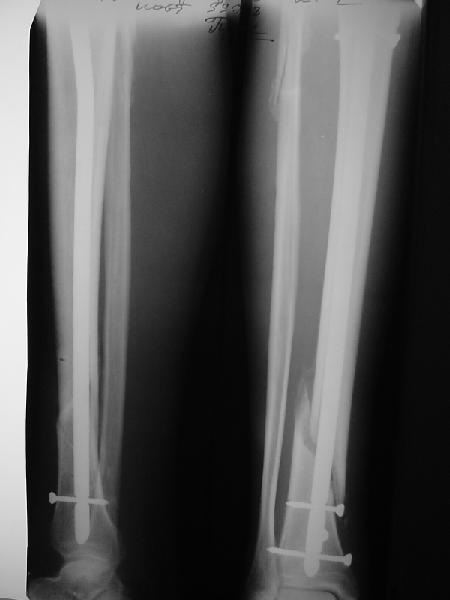

На мой взгляд, на снимках, приведённых Вами - неправильно сростающийся перелом дистальной трети большеберцовой кости, состояние после остеосинтеза интрамедуллярным гвоздём.

Как Вы пишите снимок под номером 1 - менсяц после операции, под номером 2- два месяца после операции.

Вы не послали послеоперационный снимок, поэтому трудно судить о состоянии редукции после операции.

Позвольте по поводу техники операции высказать своё мнение...

Установка с медиальной стороны гвоздя в области дистального фрагмента дополнительного шурупа помогло бы Вам репонировать и удержать перелом в анатомическом положении, предотвратило варусную деформацию и смещение по ширине.

Кстати, если можно пошлите послеоперационный снимок.

На мой взгляд внутрикостная фиксация переломов дистальной и проксимальной трети большеберцовой кости, за исключением поперечных, не очень хорошее решение вопроса, аппарат Илизарова или Тэйлора, позволяющие призвести закрытую анатомическую редукцию и отличное удержание отломков в период сращения.

Пример, приведённый Вами в нашей дискуссии по времени нагрузки после остеосинтеза не совсем удачный... Ваш больной имеет счастье, что первым согнулся проксимальный замыкающий винт, а не дистальный и гвоздь не пенетрировал голеностопный сустав.

JOM> Кстати, если можно пошлите послеоперационный снимок.

Ok. А также и следующий, в 3 месяца.